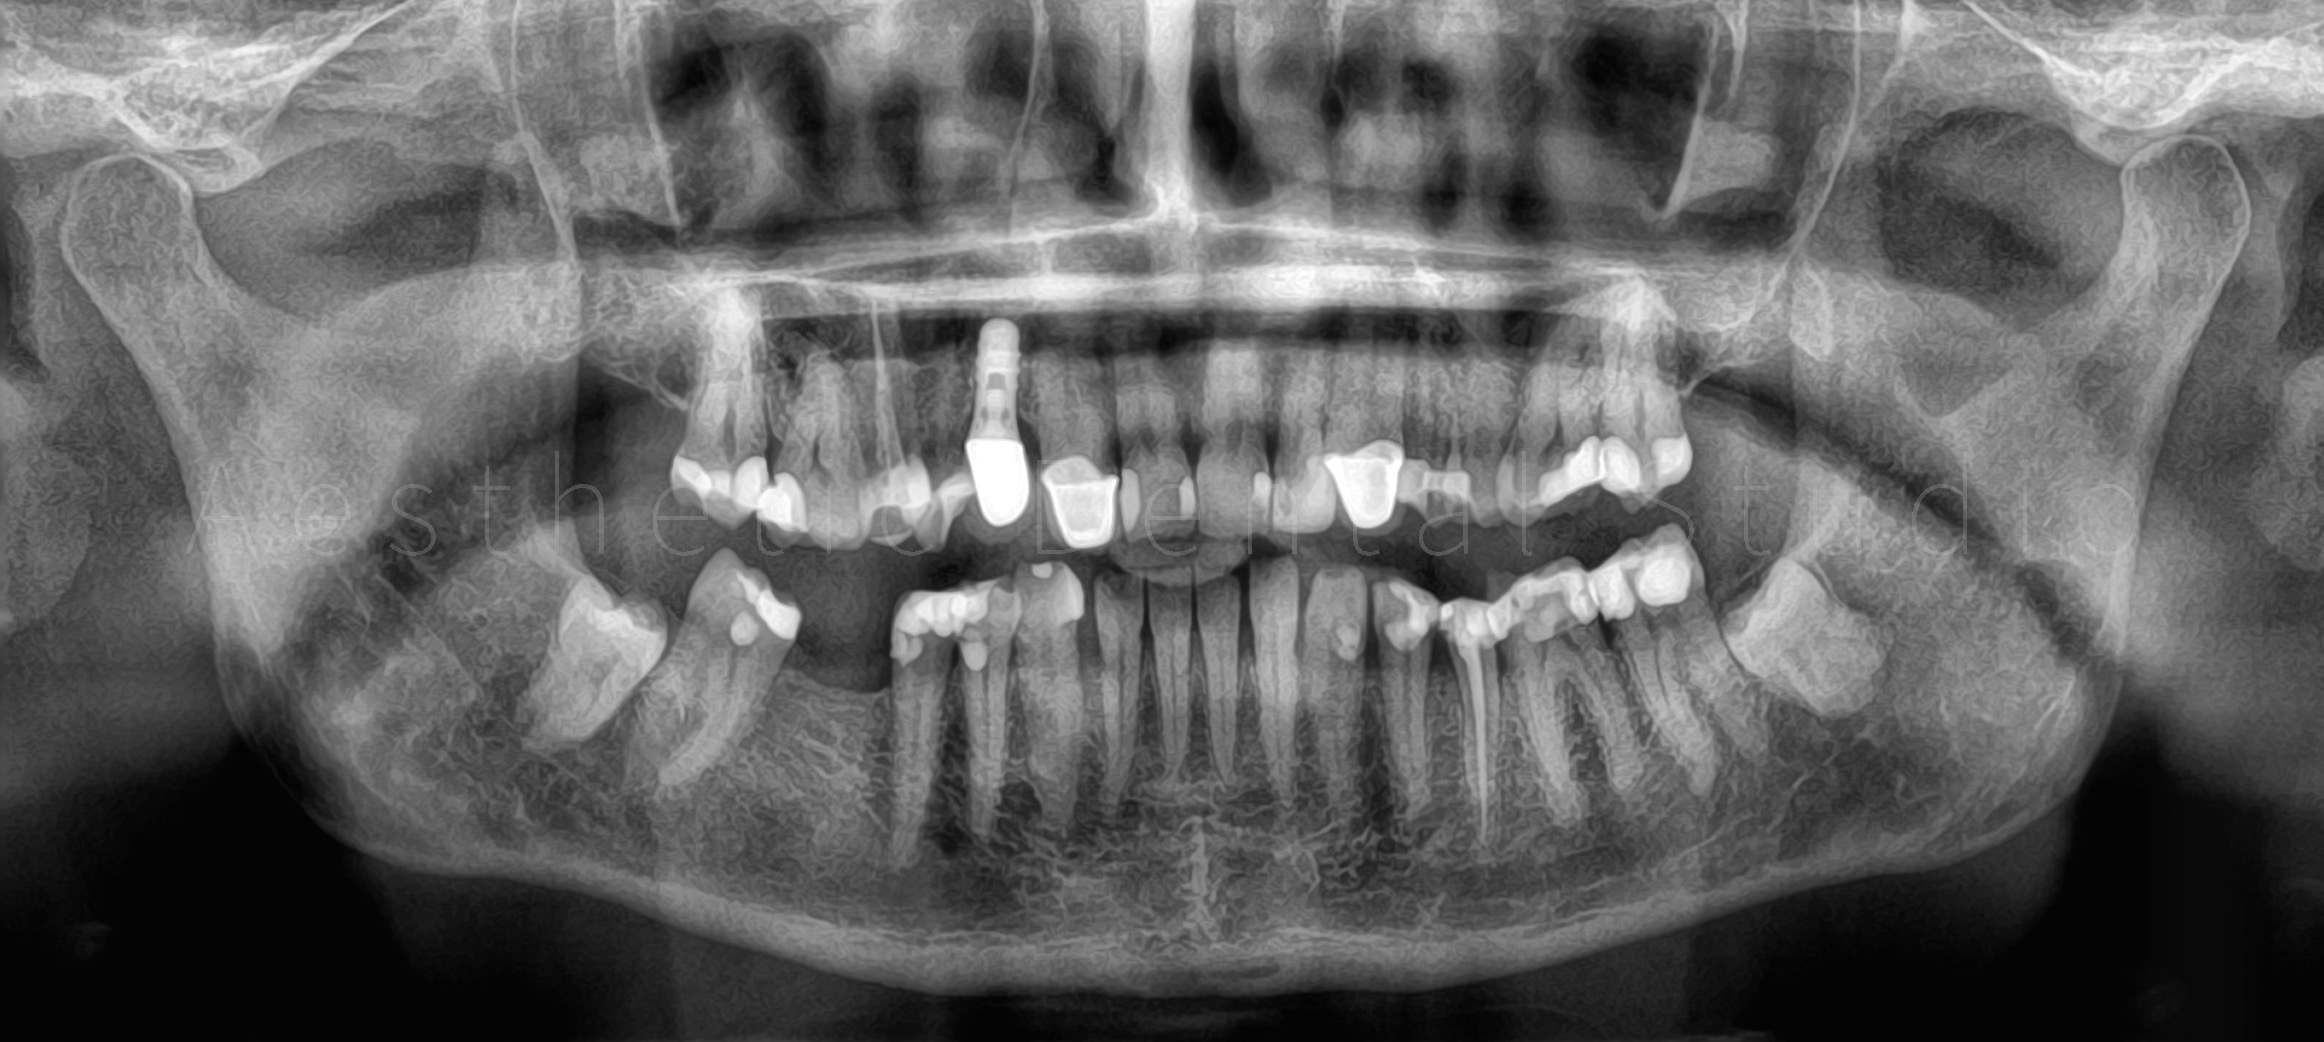

Ασθενής από τη Δυτική Ευρώπη επισκέφθηκε το Aesthetic Dental Studio κατά τη διάρκεια των διακοπών της στην Καλαμάτα, με βασικό στόχο τη βελτίωση της αισθητικής του χαμόγελού της. Η αρχική εικόνα παρουσίαζε ανομοιομορφία στο σχήμα και το χρώμα των προσθίων δοντιών, φθορά των κοπτικών άκρων και παλαιές αποκαταστάσεις που αλλοίωναν τη συνολική αρμονία του χαμόγελου. Η ασθενής ε πιθυμούσε ένα φυσικό αλλά αισθητικά άρτιο αποτέλεσμα, διατηρώντας την αυθεντικότητα των χαρακτηριστικών του προσώπου της.

Ο θεραπευτικός στόχος ήταν η αισθητική αποκατάσταση των 10 άνω προσθίων δοντιών με όψεις και ολοκεραμικές στεφάνες από ζιρκόνιο, συνδυάζοντας λειτουργικότητα και φυσικότητα. Η θεραπεία εντάχθηκε σε σφιχτό χρονικό πλαίσιο 10 ημερών, ώστε να ολοκληρωθεί εντός της παραμονής της ασθενούς στην Καλαμάτα.

Το πρώτο στάδιο της θεραπέιας περιελάμβανε την ψηφιακή ανάλυση του χαμόγελου (Digital Smile Design), όπου με τη χρήση φωτογραφιών, βίντεο και ειδικού λογισμικού, σχεδιάστηκε το νέο χαμόγελο λαμβάνοντας υπόψη τις αναλογίες του προσώπου, των χειλιών και της φώνησης. Με βάση τον ψηφιακό σχεδιασμό, δημιουργήθηκαν διαγνωστικά εκμαγεία και προσωρινές αποκαταστάσεις, ώστε η ασθενής να δοκιμάσει το μελλοντικό της χαμόγελο πριν την τελική εφαρμογή.

Ακολούθησε η προετοιμασία των δοντιών και η λήψη ψηφιακών αποτυπωμάτων με ενδοστοματικό σαρωτή, τα οποία στάλθηκαν στο συνεργαζόμενο εργαστήριο. Εκεί σχεδιάστηκαν και κατασκευάστηκαν ολοκεραμικές αποκαταστάσεις υψηλής αισθητικής, με απόλυτη ακρίβεια εφαρμογής και χρωματική φυσικότητα. Οι τελικές όψεις και στεφάνες τοποθετήθηκαν στα δόντια της ασθενούς μετά από προσεκτικό έλεγχο αισθητικής, φώνησης και λειτουργίας, επιτυγχάνοντας απόλυτη εναρμόνιση με το πρόσωπο.